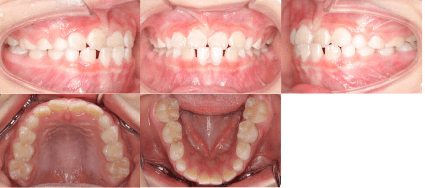

<治療後>

- 初診時年齢:7歳2ヶ月

- 主訴:前歯のかみ合わせが反対

- 診断:前歯部反対咬合

- 抜歯の有無:非抜歯

- 治療内容:マウスピース型カスタムメイド矯正歯科装置(製品名インビザライン 完成物薬機法対象外)を使用して主訴である前歯の交叉咬合を改善しました。

- 治療期間:6ヶ月 通院回数6回

- リスク:矯正歯科装置を付けた後しばらくは違和感、不快感、痛みなどが生じることがあります。

- 治療中は矯正歯科装置が歯の表面に付いているため食物が溜りやすく、また歯が磨きにくくなるため、むし歯や歯周病が生じるリスクが高まります。

- 歯を動かすことにより歯根が吸収して短くなることや歯肉がやせて下がることがあります。

- 費用:40万円